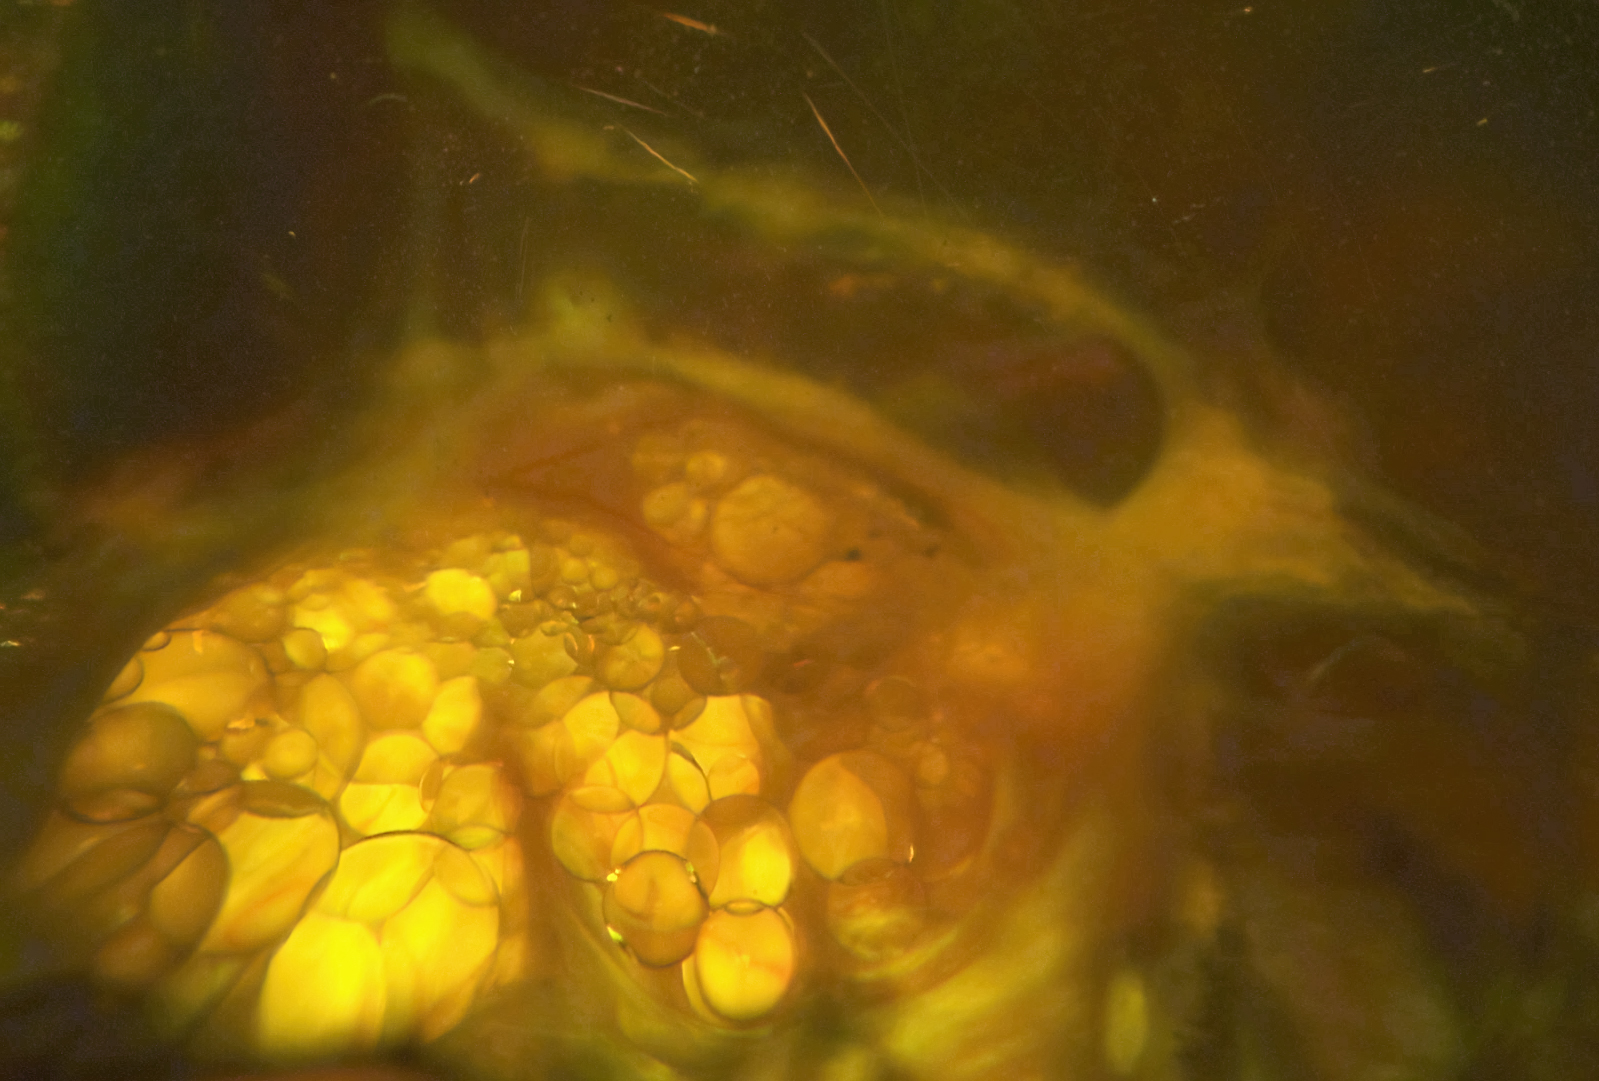

Subretinal perfluorocarbon liquid (PFCL). Bubbles of PFCL on structural ...

In vitro experiment. a A perfluorocarbon liquid (PFCL) bubble in a ...